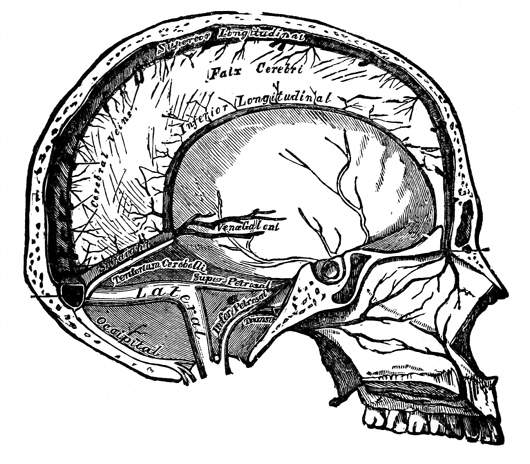

Fig. 3—Lymphatics of the head and neck.

B, the thoracic duct.